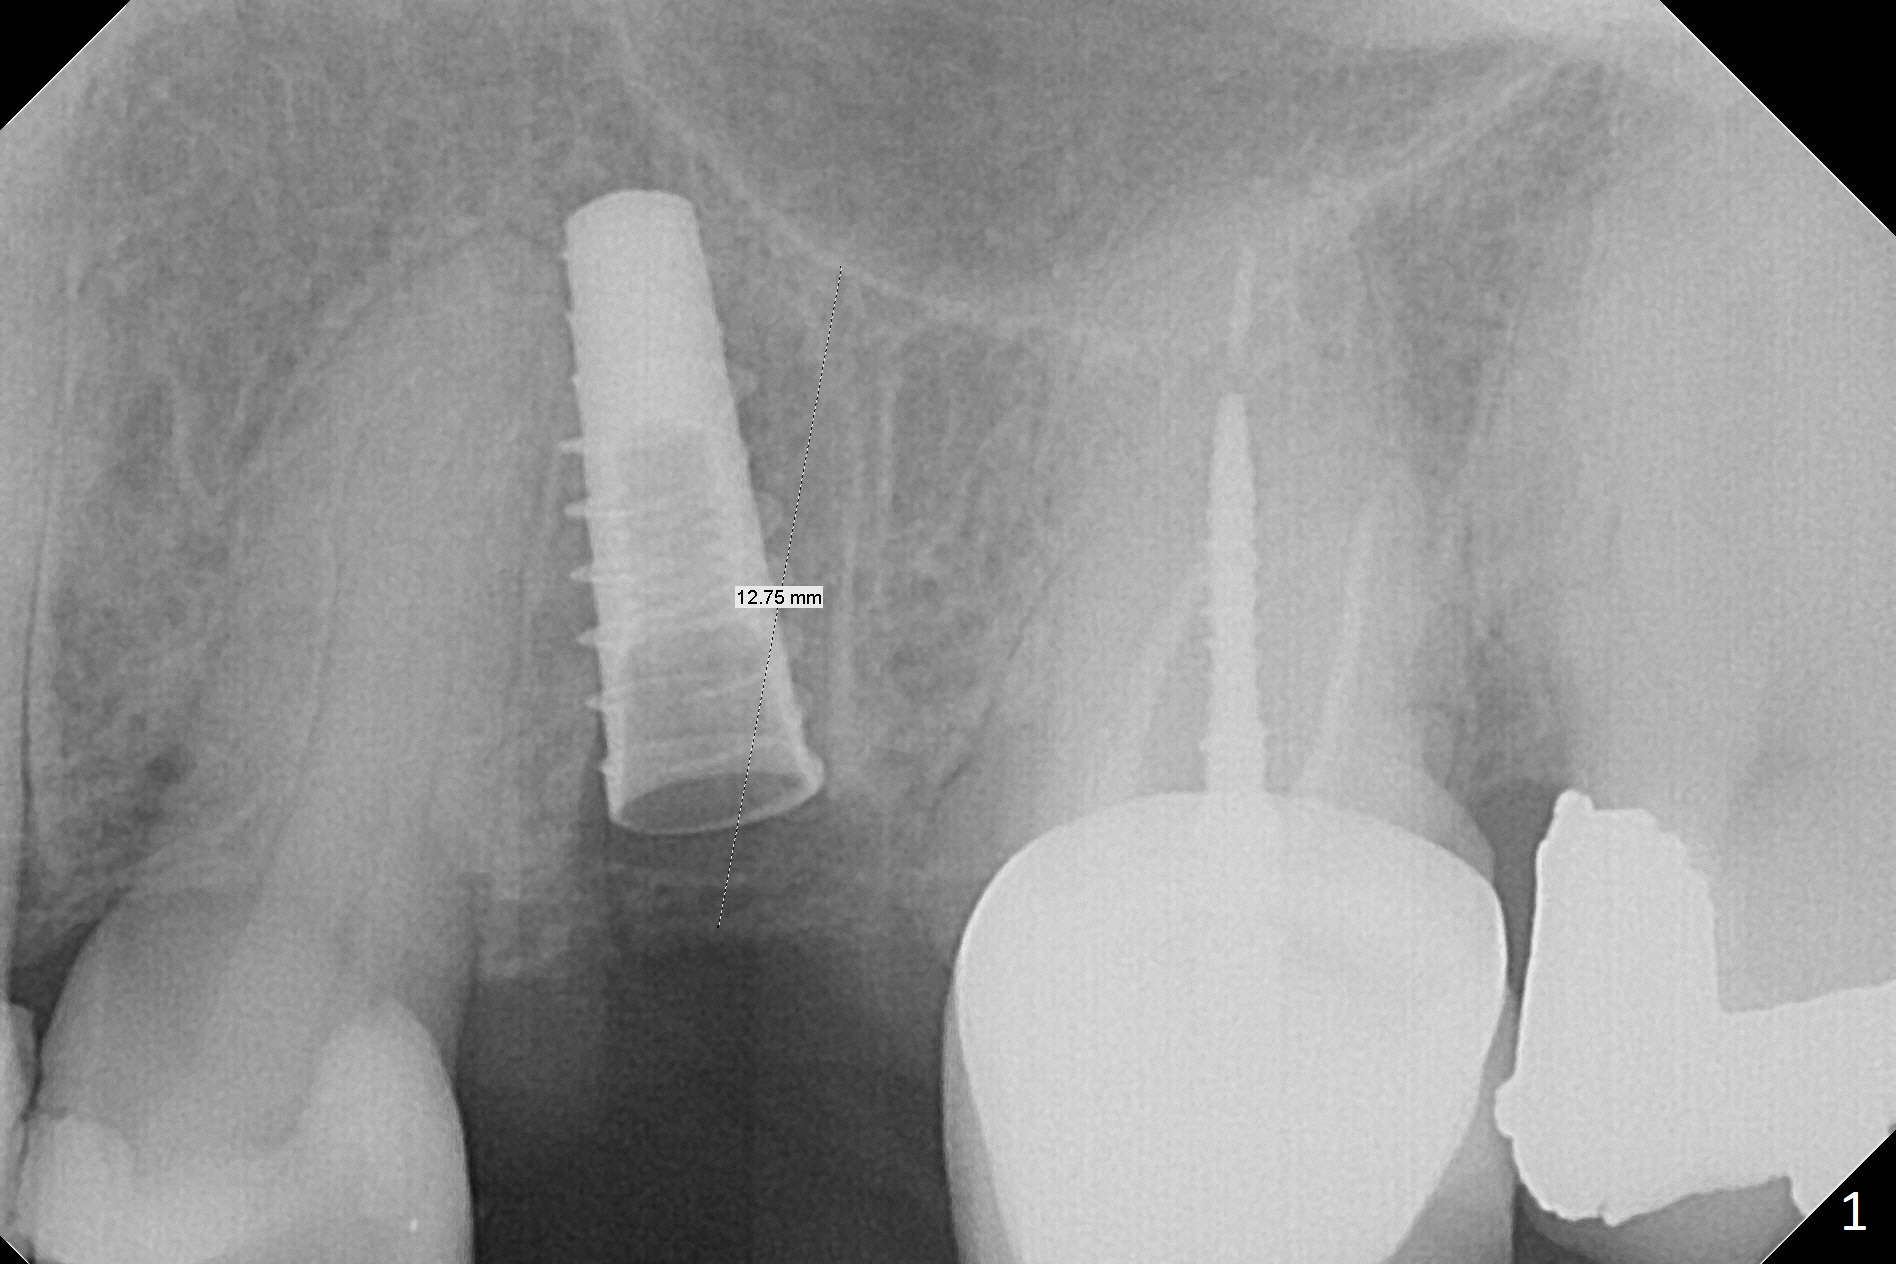

Since the apical native bone is limited at #13 after extraction, no PA is taken until a 4x11 mm dummy implant is placed after 1.6 mm and 3.3 mm drills for 13 mm (Fig.1). After using Lindamann bur to move the osteotomy distal and reusing 3.3 mm drill, the trajectory of a 4.5x11 mm IBS dummy implant improves (Fig.2,3 with low stability). When the implant is removed, the buccal portion of the socket is found to be perforated (Fig.4 P). Although the reason for the perforation is unknown, it is repaired by insertion of a piece of PRF plug, followed by allograft. #1 and 2 in Fig.4 represent the 1st and 2nd osteotomies, as shown in Fig.1 and 2, respectively. The trajectory of the final 5x13 mm implant is acceptable (Fig.5-7, different angulations), so is insertion torque (45 Ncm). After placing a 5.5x4(4) mm abutment, an immediate provisional is fabricated (Fig.8 P) with occlusal clearance (*). The interdental papillae remain in place 12 days postop (Fig.9 *). There is no sign of postop sinus infection. The provisional is loose 18 days postop; the abutment is changed to 5x4(3) mm (Fig.10). It is difficult to catch the mesial margin of the abutment for impression 4 months postop, due to poor oral hygiene and the short cuff (3 mm, Fig.11). The appointment for impression is rescheduled with emphasis on oral hygiene and no wearing the provisional for a few days prior to next appointment. Bone has grown into the space between the 1st and 2nd threads 5 months post cementation (Fig.12) and the bone is normal, solid and dense 2 years 11 months post cementation (Fig.13 >). There is mesial open margin of the tooth #14 (Fig.13,14 *).